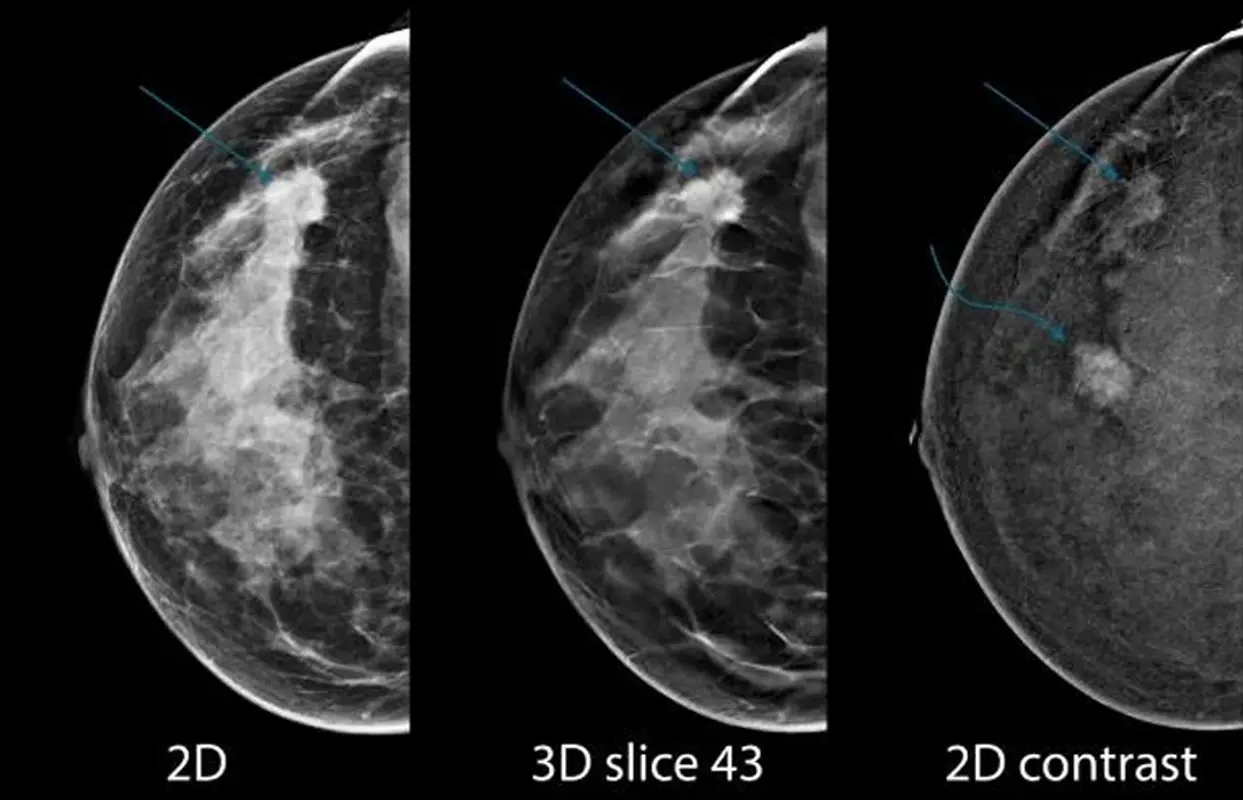

ماموگرافی معمولی یا ماموگرافی دو بعدی شامل گرفتن تصاویر اشعه ایکس از پستان از دو زاویه بالا به پایین و پهلو به پهلو است. این تصاویر نمای صافی از بافت پستان ارائه میدهند که گاهی اوقات میتواند منجر به همپوشانی بافتها شود و نمای واضح ناهنجاریها را مبهم میکند. از سوی دیگر، ماموگرافی هالوژیک یک تکنیک تصویربرداری سه بعدی است. چندین عکس با اشعه ایکس از سینه از زوایای مختلف می گیرد و آنها را به صورت یک تصویر سه بعدی بازسازی میکند. این به رادیولوژیست ها اجازه میدهد تا بافت سینه را لایه به لایه بررسی کنند و تاثیر همپوشانی بافتها روی هم را کاهش دهند.

تصاویر سه بعدی تولید شده توسط ماموگرافی هالوژیکی جزئیات فوق العاده واضحی را ارائه میدهند که امکان تجسم بهتر توده ها و اعوجاج های مرتبط با سرطان را فراهم میکند. این افزایش دید منجر به اطمینان بیشتر تشخیصی برای رادیولوژیستها و تشخیص دقیقتر برای بیماران میشود.